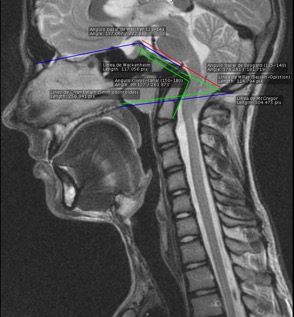

È conosciuta con il nome di Platibasia l’anomalia ossea che consiste nell’appiattimento della base del cranio, che si manifesta nell’apertura dell’angolo di Boogard alla base del cranio. Di norma, il valore di quest’angolo oscilla tra 115° e 140°. Esiste platibasia quando quest’angolo supera i 140°. Inoltre possono essere presi in considerazione altri angoli di riferimento, per esempio quello di Bull (di norma di 13°).

È possibile che qualche diagnosi sia emessa mediante una Risonanza Magnetica Nucleare- RMN encefalica o cranica- anche se, una volta individuata la malformazione, per il suo controllo ottimale è indicata la TAC.

Fig.2 Immagine di Platibasia in una RMN.